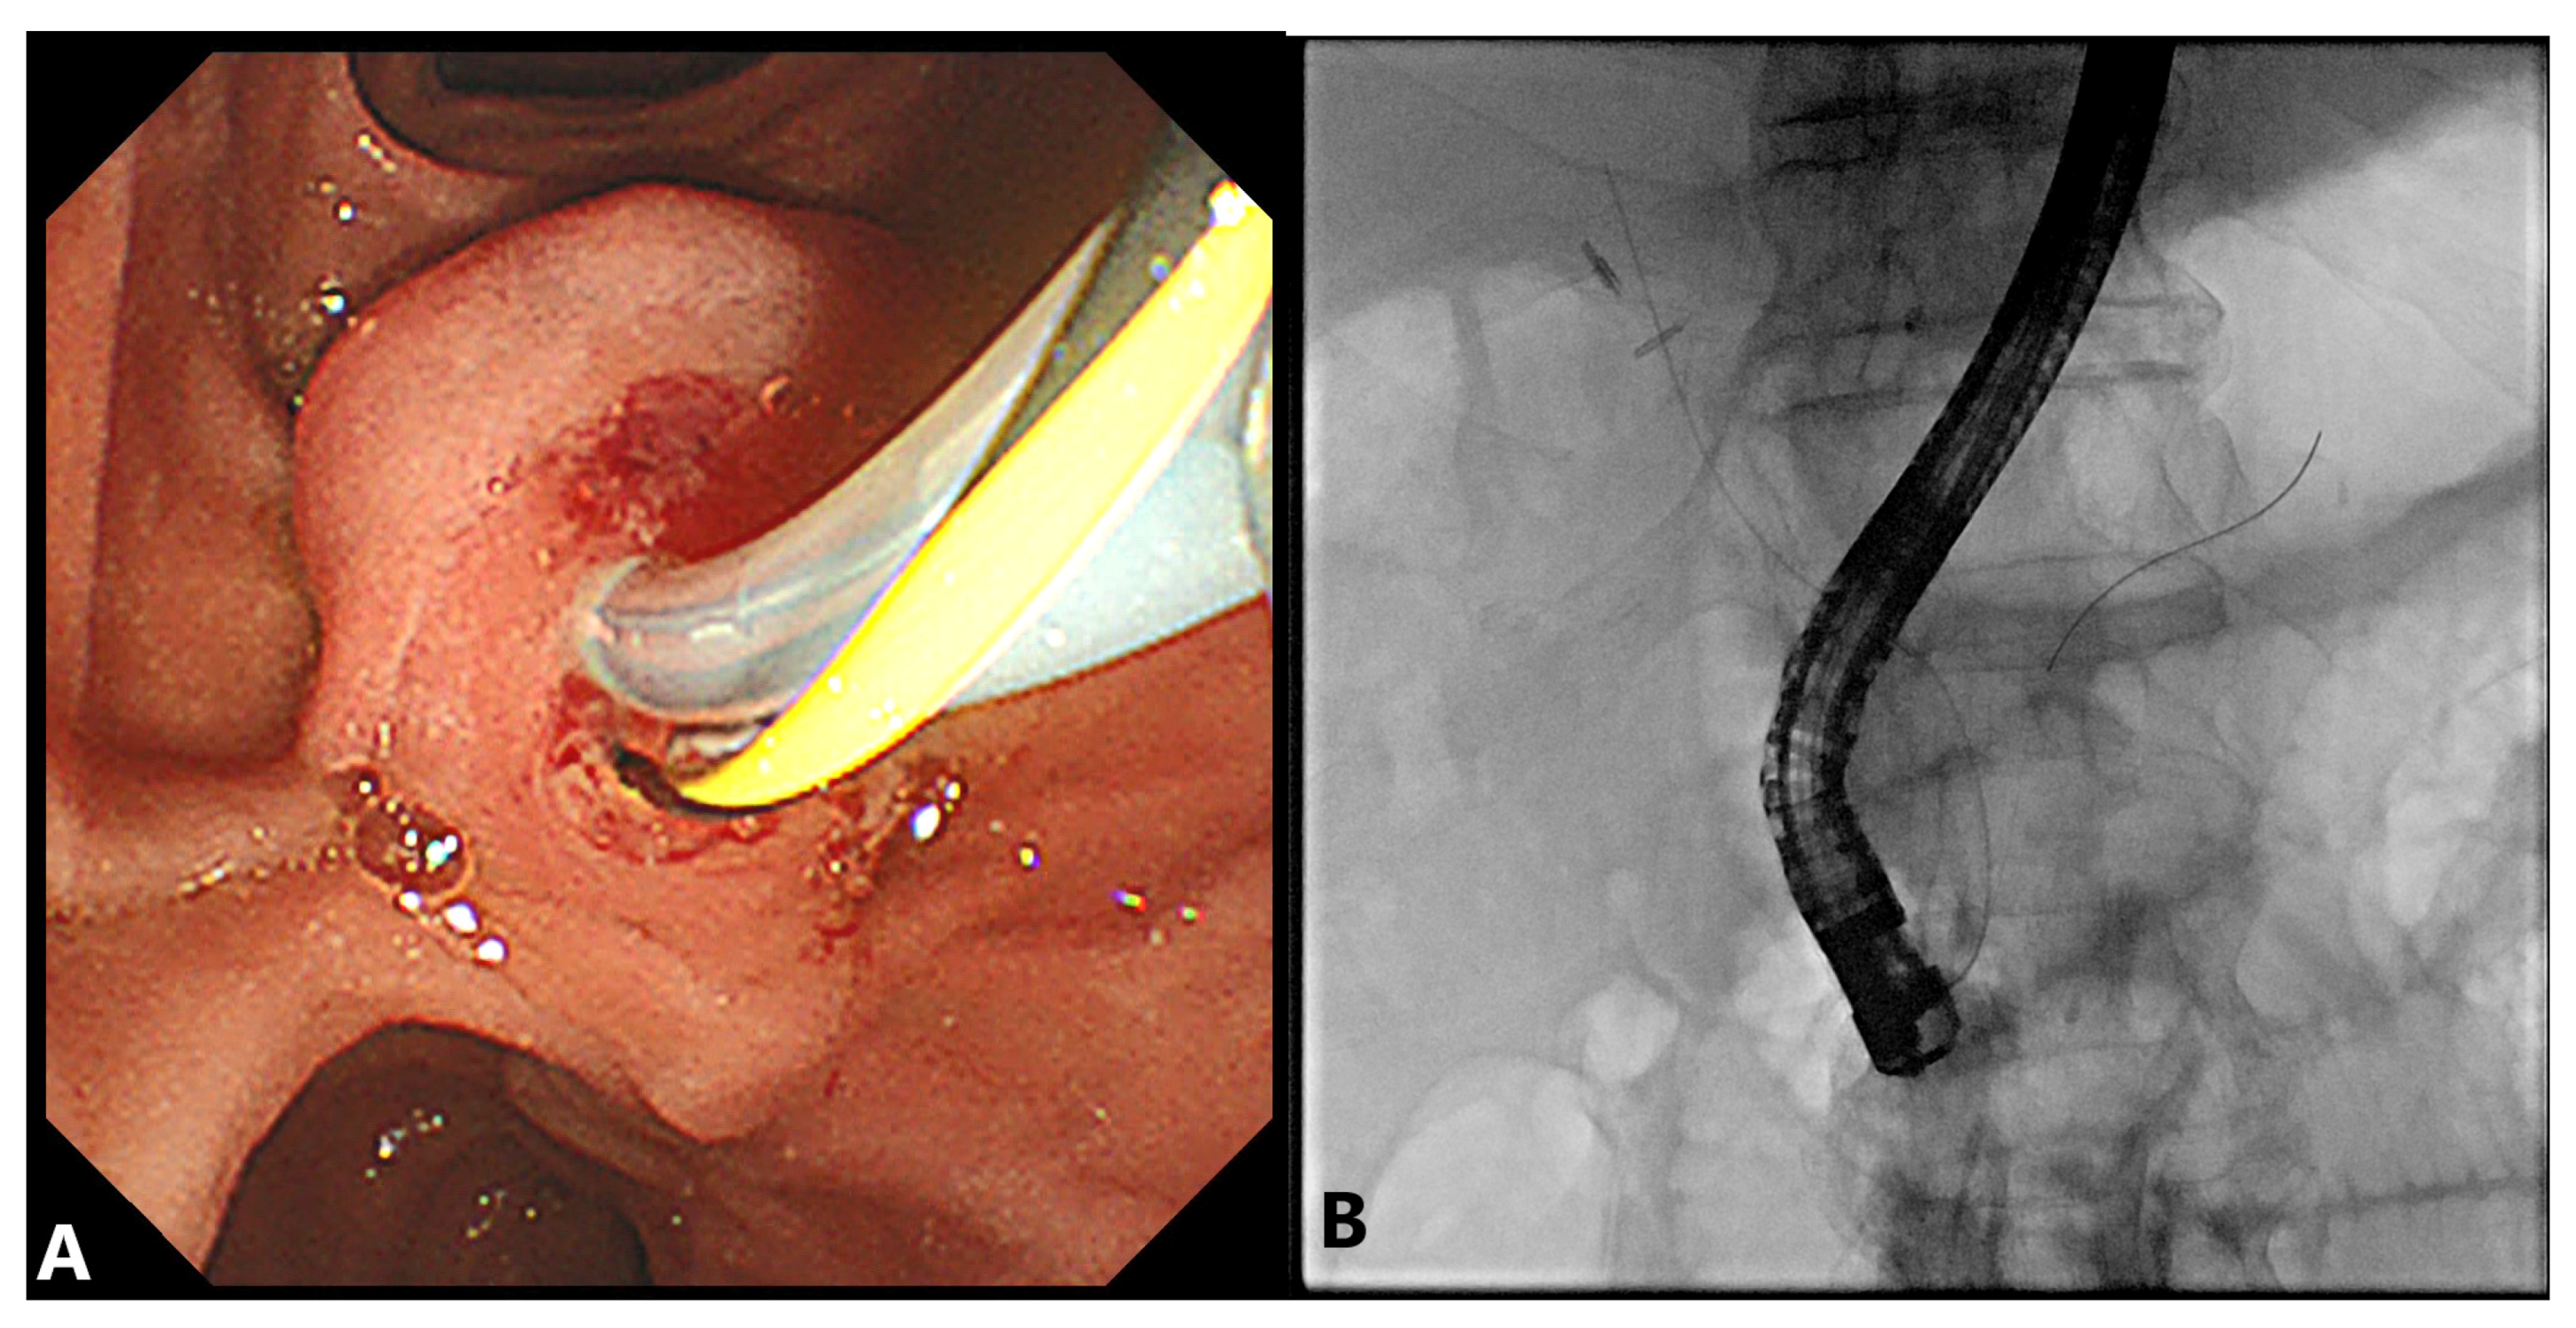

2.2. Precut Papillotomy